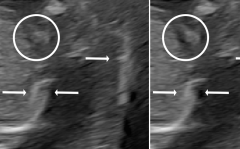

Maximization of coherence in a region adjacent to a strong scatterer is then susceptible to an erroneous speed of sound selection because this will actually lead to a higher sidelobe level here (see illustration in Fig. 3).

Such problems can be mitigated by spatial expanding of the coherence values in each of the coherence images before selecting the maximum across different sound speeds. Spatial expansion can be implemented using an image processing technique called percentile or rank filtering [20]. This filtering operation is performed with a 2D kernel sliding over the image picking a high percentile coherence value within the kernel. The 50th percentile and 100th percentile versions of such a filter are equivalent to a median filter and image dilation, respectively. The 90th percentile is used for the methods in this paper. Figure 3 illustrates how the percentile filter works by practically expanding the main lobe of the Point Spread Function (PSF) of the system, thus ensuring that the maximum coherence value is also selected off-axis from a strong scatterer.

Refer to caption

(a) No percentile filter.

(b) With percentile filter.

Figure 3: Illustration of Point Spread Function (PSF) beamformed with correct and wrong speed of sound. The bar on top in (a) shows that the max value is chosen to be the PSF using correct sound speed in the mainlobe, but incorrect sound speed in the sidelobes. After percentile filtering in (b) the correct sound speed is chosen in the sidelobes as well.